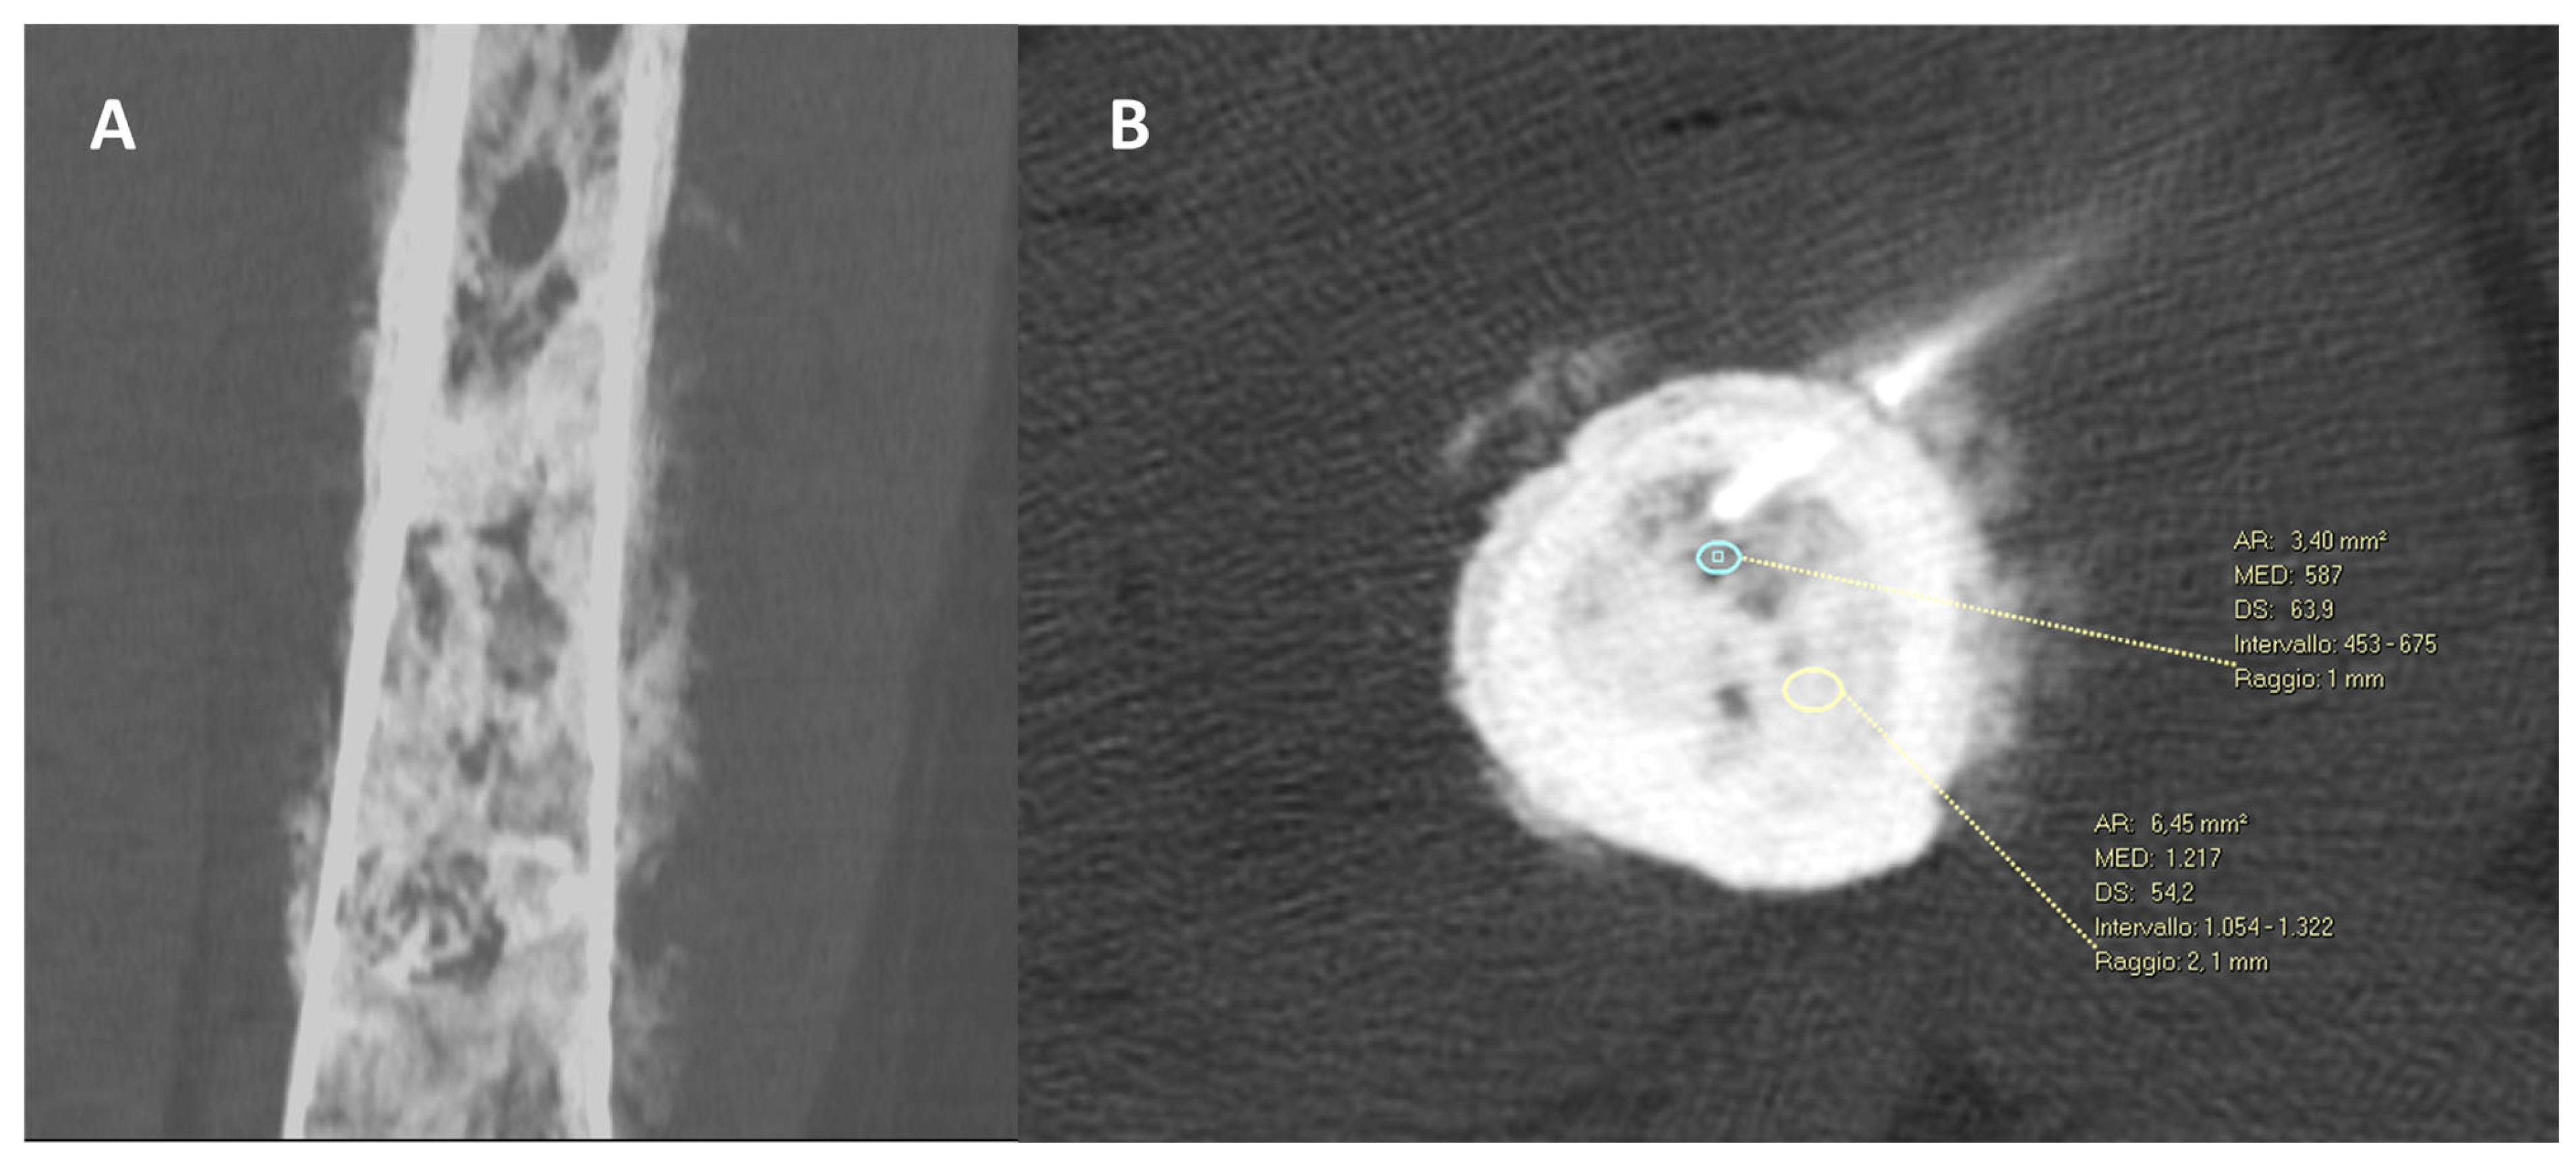

- Donners, R.; Fotiadis, N.; Figueiredo, I.; Blackledge, M.; Westaby, D.; Guo, C.; de la Maza, M.d.l.D.F.; Koh, D.-M.; Tunariu, N. Optimising CT-guided biopsies of sclerotic bone lesions in cancer patients. Eur. Radiol. 2022, 32, 6820–6829. [Google Scholar] [CrossRef]

| Short sample (short needle penetration in the tumor/perpendicular needle trajectory) | Large sample (long needle penetration in the tumor/oblique needle trajectory) |